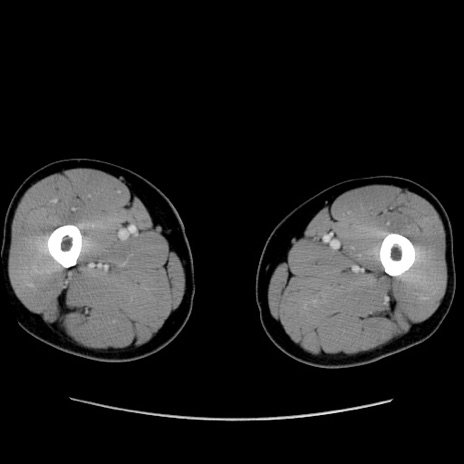

症例34(横断像)

【症例】60歳代 男性

【主訴】右鼠径部膨隆

【現病歴】1年程前より右鼠径部膨隆あり。自己にて還納可能だったため放置していた。3時間前より右鼠径部の脱出を認め、還納困難となり受診。

【既往歴】高血圧

【身体所見】右鼠径部に小児頭大の膨隆あり。弾性硬であり、用手還納は困難。左鼠径部にも膨隆を認める。脱出はなし。